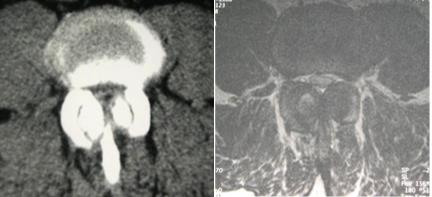

Se trata de un estrechamiento progresivo del "tubo" por el que bajan los nervios desde el cerebro a las piernas. Estos nervios son los "cables" de transmisión de información de sensibilidad desde las piernas al cerebro y las órdenes de movimiento desde el cerebro a las piernas; por eso estos pacientes sienten zonas de los pies o de las piernas dormidas y, a veces, pierden fuerza para algunos movimientos concretos.

Además, al perder altura los discos por esa deshidratación, los fuertes ligamentos amarillos (en la parte posterior del tubo) se repliegan, abultando hacia dentro del tubo del que hablábamos antes. Ese tubo es el canal medular, por el que pasan la médula y los nervios.

La palabra "estenosis" significa "estrechez". Así ya tenemos qué significa y cómo se va formando la estenosis de canal.

Escuchando al paciente. Hay que acompañarlo con pruebas de imagen como radiografías y resonancia magnética o TAC.